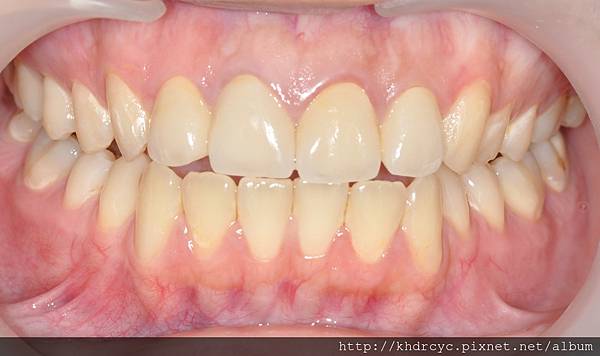

感謝仁武的C小姐對療程相當配合

欣美牙醫在短時間內達成任務

拍完宣傳照隔天仁武的C小姐

與經紀人特地來欣美牙醫道謝

不但牙齒變美變白連口氣都改善了

笑起來也更能自信的露牙齒

唱歌也不用顧忌